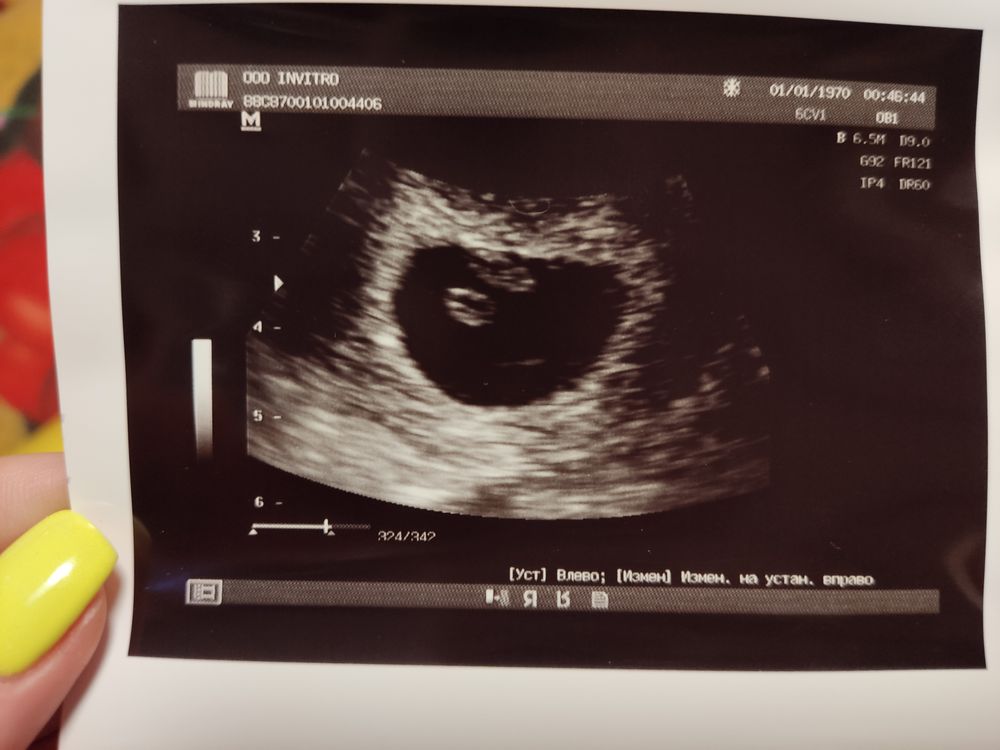

Делала УЗИ, срок по УЗИ 6 нед и 5 дней.

Объясните мне, неопытной😁, что да где тут? Не понимаю где эмбрион? Почему 2 светлых пятнышка?

По центру желточный мешочек у оболочки(края)-ваш малышочек🥰Лёгкой Б💐

Эмбриончик в этом центральном чёрном кружочке))) такое светлое пятнышко))) ничего, всему своё время, первое время я тоже ничего не понимала, узиста расспрашивала

Одно пятнышко более круглое - желтое тело, питающее эмбрион. Второе более вытянутое - эмбриончик

Елена, вы, наверное, желточный мешочек имели в виду? Желтое тело в яичнике находится.